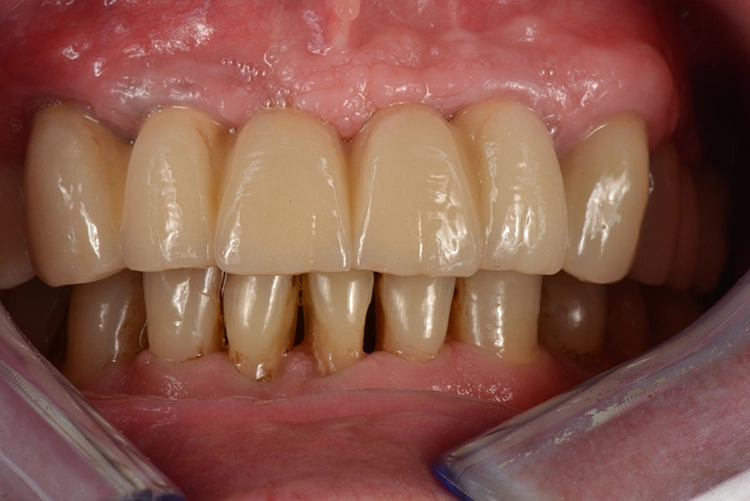

Die Freilegung der Implantate erfolgte mit minimalinvasiver Stichinzision. Die Verschlussschrauben wurden entfernt und Gingivaformer eingesetzt, um das Weichgewebe auszuformen. Die ursprüngliche Teleskopprothese wurde im Bereich der Gingivaformer ausgeschliffen und mit einer Gaumenplatte erweitert.

So konnte sie als Interimsversorgung, verankert auf den Zähnen 23 und 24, über den Gingivaformern als Interimsersatz genutzt werden und sich das Weichgewebe unbelastet um die Implantate herum ausformen. Einige Wochen später – wiederum verzögert durch einen Campingaufenthalt – konnte auf dem mittlerweile befestigten und stabilen Weichgewebe für die Herstellung der definitiven Restaurationen abgeformt werden. Hier ist von Vorteil, dass die Conelog Abformpfosten nicht in den Konus des Implantats eingreifen, sondern auf der Implantatschulter aufliegen, wodurch ein Höhenversatz bei der Abformung vermieden wird.

Während die Zähne 23 und 24 mit keramischen Einzelkronen versorgt wurden, erfolgte die definitive Restauration der Implantate über drei VMK-Brücken auf gefrästen NEM-Gerüsten über individuellen Titanabutments: von 17 auf 15, von 14 auf 22 und von 25 auf 27. Die Materialkombination wurde unter anderem auch in Hinblick auf ein vermindertes Chipping-Risiko gegenüber einer Versorgung mit Zirkon gewählt.